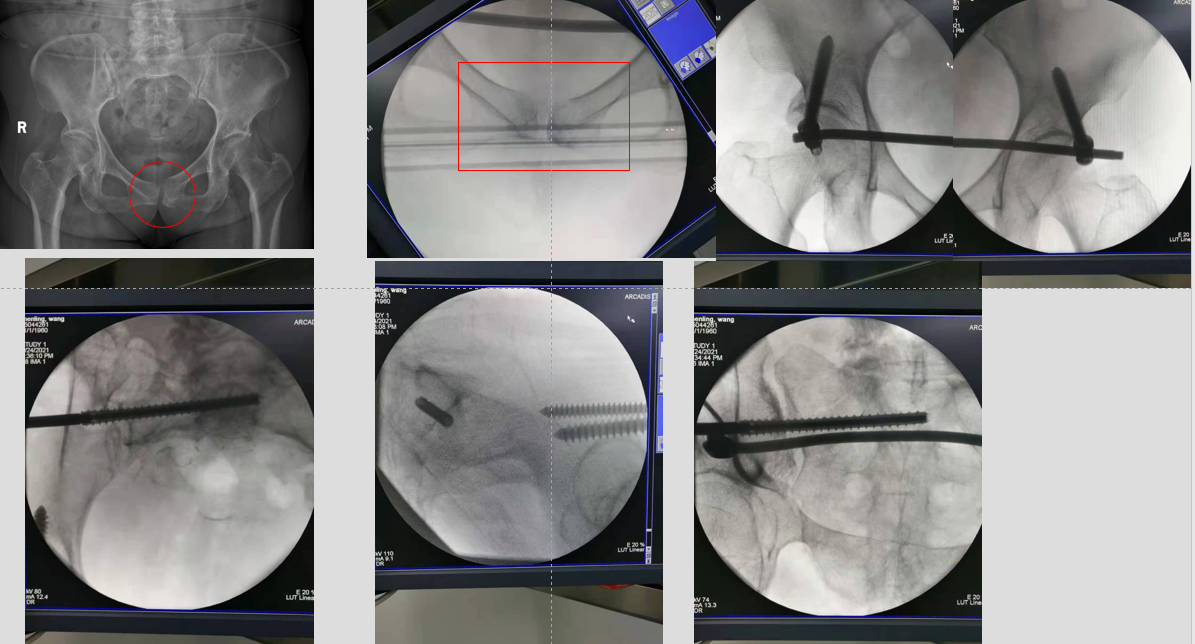

在上级专家指导下,科室团队确定了现行给予骨盆内置外架恢复骨盆稳定,再给予经皮骶髂螺钉植入固定后环的手术方案。

◆术后伤口

◆术后情况

◆术后复查影像